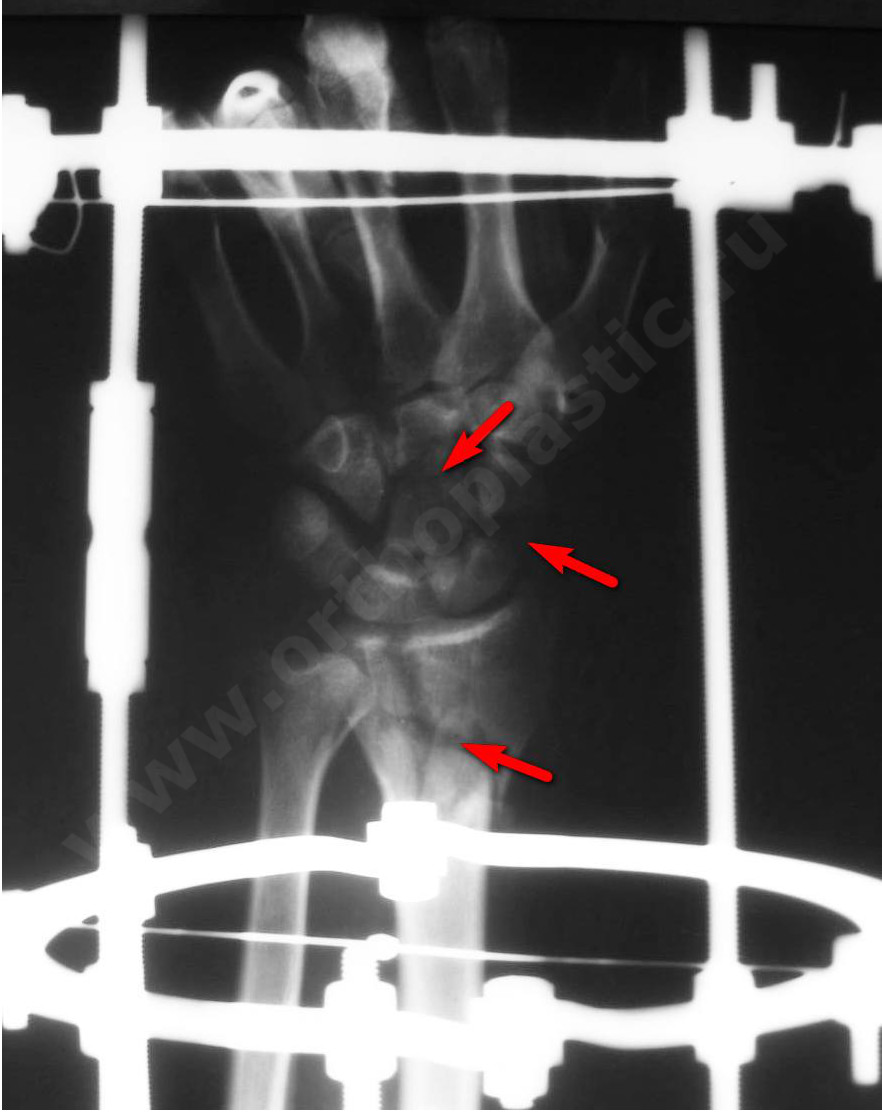

1- рентгенограмма пациента К. с переломом ладьевидной кости, переломом головчатой кости, перелом дистального метаэпифиза лучевой кости

3- рентегнограмма пациента К. через 4 месяца после травмы, переломы срослись